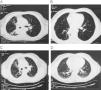

Se presenta el caso de un varón de 47 años, fumador de 30 cigarrillos diarios que ingresó en neumología por clínica insidiosa de tos con expectoración hemoptóica de escasa cuantía, febrícula, pérdida de peso y de apetito de más de un mes de evolución. La TAC de tórax (fig. 1A y B) mostró una masa hiliar derecha, con afectación de lóbulos inferior, medio y superior, que englobaba a todas las estructuras hiliares, causando compresión sobre el bronquio intermediario, sin obliterarlo y con aéreas de neumonitis distal con broncograma aéreo. No se visualizaron adenopatías mediastínicas ni hiliares. Tras realizar 2 broncoscopias que resultaron negativas para células neoplásicas (fragmentos de mucosa bronquial con leve inflamación crónica inespecífica y metaplasma escamosa superficial) y 2 PAAF de pulmón también negativas para malignidad, se solicitó PET-TAC que mostró aumento de captación a nivel parahiliar y paramediastínico derecho (depósito aumentado del trazador localizado en región parahiliar derecha que se extiende hacia el mediastino posterior ipsilateral y presenta una morfología irregular con límites imprecisos, un tamaño de 8×5×6 y una captación heterogénea con un SUV máximo de 11). Se entiende por SUV: Estándar Uptake value<2.5/SUV del parénquima pulmonar normal: 0,3. Con la sospecha firme de neoplasia de pulmón5 pendiente de filiar se derivó a cirugía torácica para diagnóstico definitivo y tratamiento oportuno. Tras toracotomía derecha y toma de muestras de la lesión del lóbulo superior derecho y lóbulo inferior derecho se llegó al diagnostico definitivo de bronquiolitis obliterante con neumonía organizada criptogenética.

Tras pautar tratamiento con Prednisona 1mgr/kg de peso/día y después de una pauta descendente prolongada, (un año de tratamiento), el paciente quedó asintomático y en la última TAC torácico de control (fig. 1C y D), la lesión central parahiliar derecha había desaparecido; aunque se visualizaban bronquiectasias residuales en segmento anterior del lóbulo superior derecho y en superior del lóbulo inferior derecho. Tras un año sin tratamiento no se han producido recidivas.